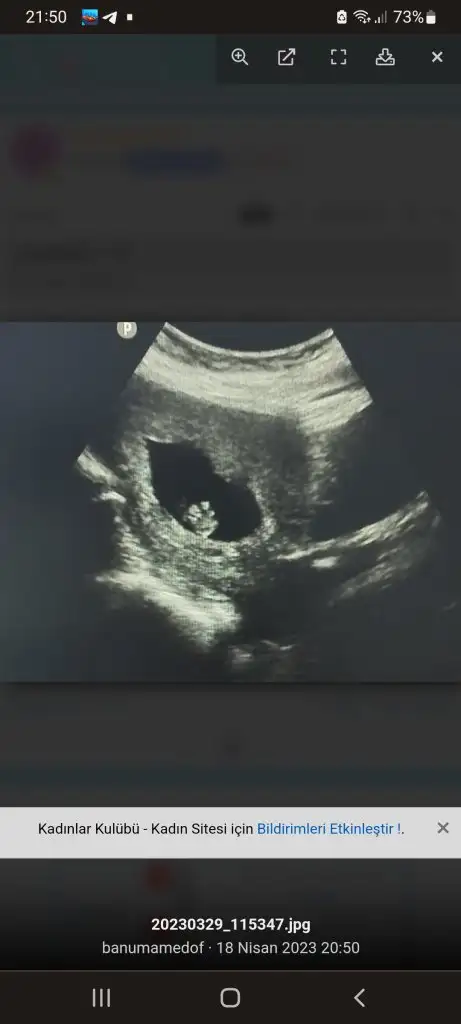

Merhaba kızlar bugün 7+4 olduk v3 kalp atışlarını dinledik çok şükür 🙏buda vajinal ultrason . Cinsiyet tahmini yapan arkadaşlar vardı yardımcı olur musunuz çok merak ediyorum cinsiyetini 😊

Eklentiler

• 20230419_110937.webp

20230419_110937.webp

35,4 KB · Görüntüleme: 73